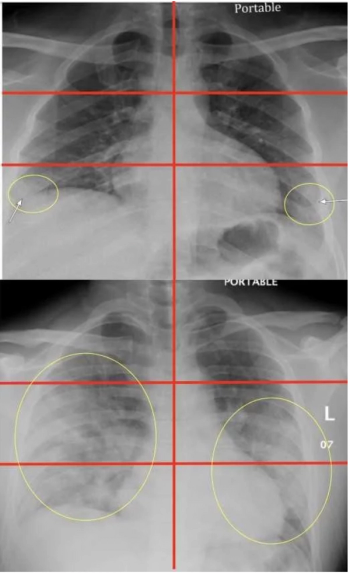

A volumetric analysis of lung consolidation can help providers make care management decisions and, potentially, pinpoint which patients are most likely to die in the hospital.